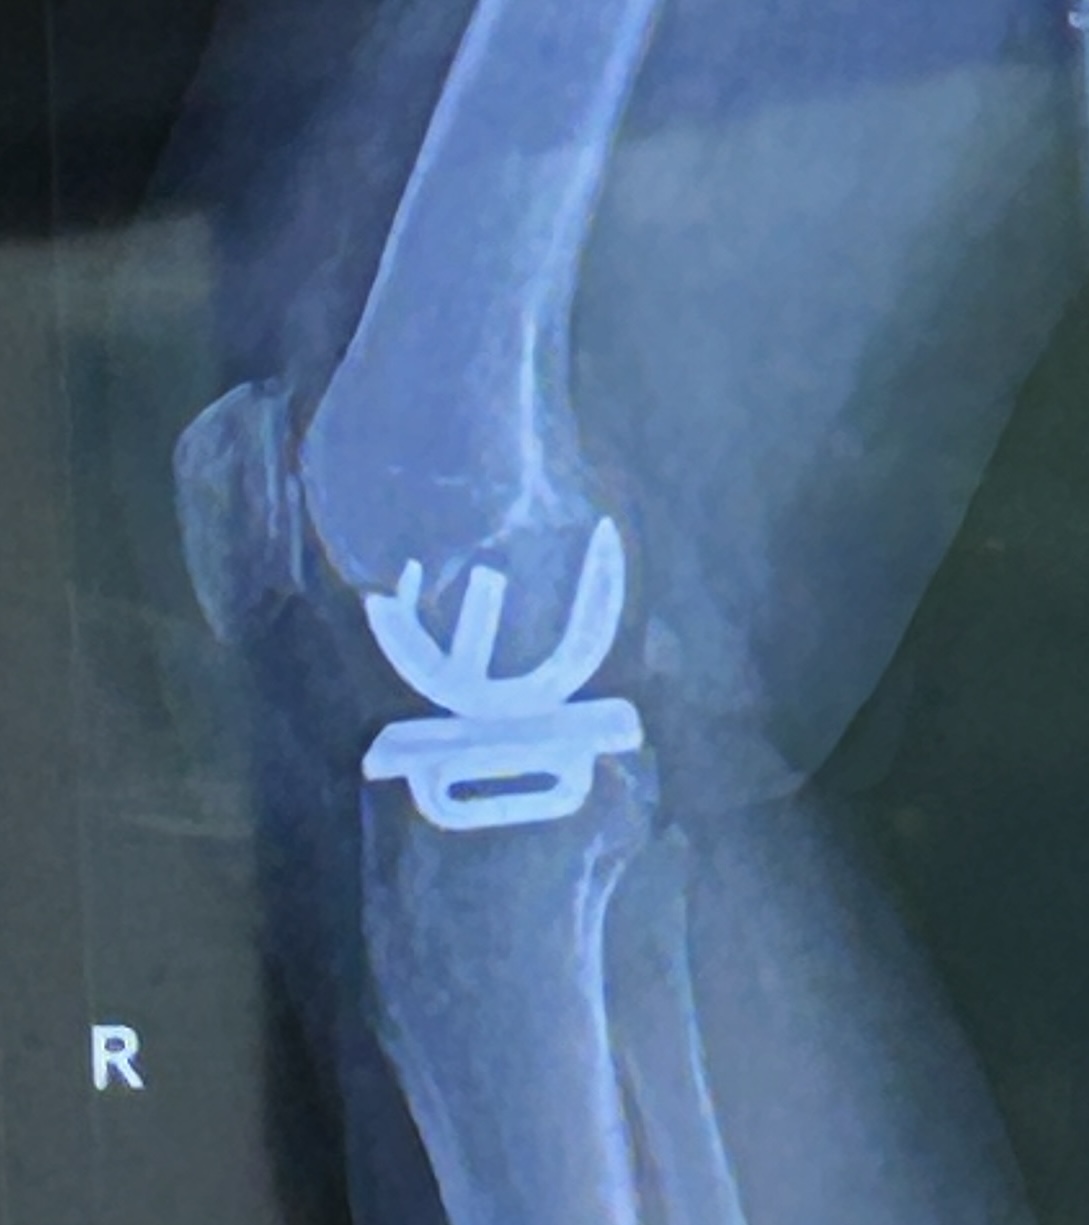

2025: Bij het begin van 2026 past een korte terugblik op een voor ons bewogen jaar. Het jaar startte voor Joyce met herstellen van een staaroperatie. Het kijken gaat beter, maar helaas heeft zij er wel het droge ogen syndroom aan overgehouden. Dus elke dag meermalen druppelen. Met vermeende hartklachten werd Joyce in mei opgenomen op de spoedeisende hulp. Het bleek gelukkig vals alarm. In juli kreeg Joyce een nieuwe (halve) knie. Deze geeft na een half jaar en tientallen fysiobehandelingen nog steeds problemen. De knie blijft dik. Buigen gaat goed, maar lopen blijft een pijnlijke activiteit. Volgens de artsen kan dat nog minimaal een half jaar duren en het is zelfs onzeker of het ooit beter wordt. O ja, Joyce ging voor grijs. Met die operatie is ze inmiddels wel helemaal tevreden.